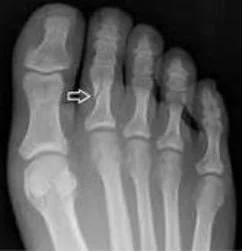

Forefoot phalanx fractures are fractures of the toe bones, which play an important role in balance, push-off, and overall gait mechanics. These injuries range from simple, non-displaced fractures to more complex injuries involving joint surfaces or multiple toes.

Each toe is composed of small bones called phalanges, which are connected by joints and supported by surrounding soft tissues. The great toe has two phalanges, while the lesser toes have three. Fractures may involve the shaft of the bone, the joint surface, or the tip of the toe.

Diagnosis begins with a focused clinical evaluation, assessing swelling, bruising, tenderness, alignment, and the ability to bear weight or move the affected toe. Careful examination is important to identify rotational deformity or joint involvement.

Imaging is used to confirm the diagnosis. X-rays are typically sufficient to identify the fracture pattern, degree of displacement, and joint involvement. Advanced imaging is rarely required but may be considered in complex or unclear cases.